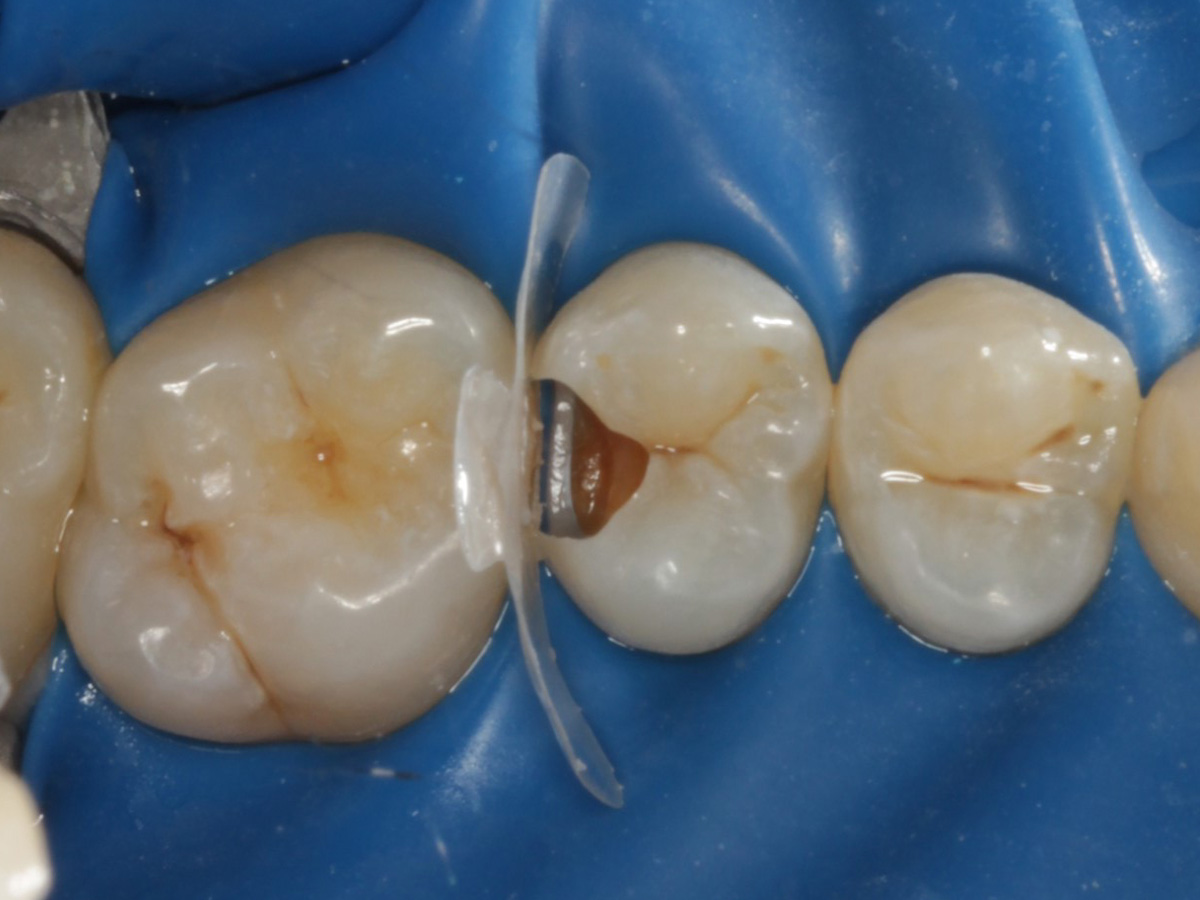

Abbildung 17

Zahnseidenkontrolle: kein Überschuss, satter Kontaktpunkt

Abbildung 18

Fertige Restauration